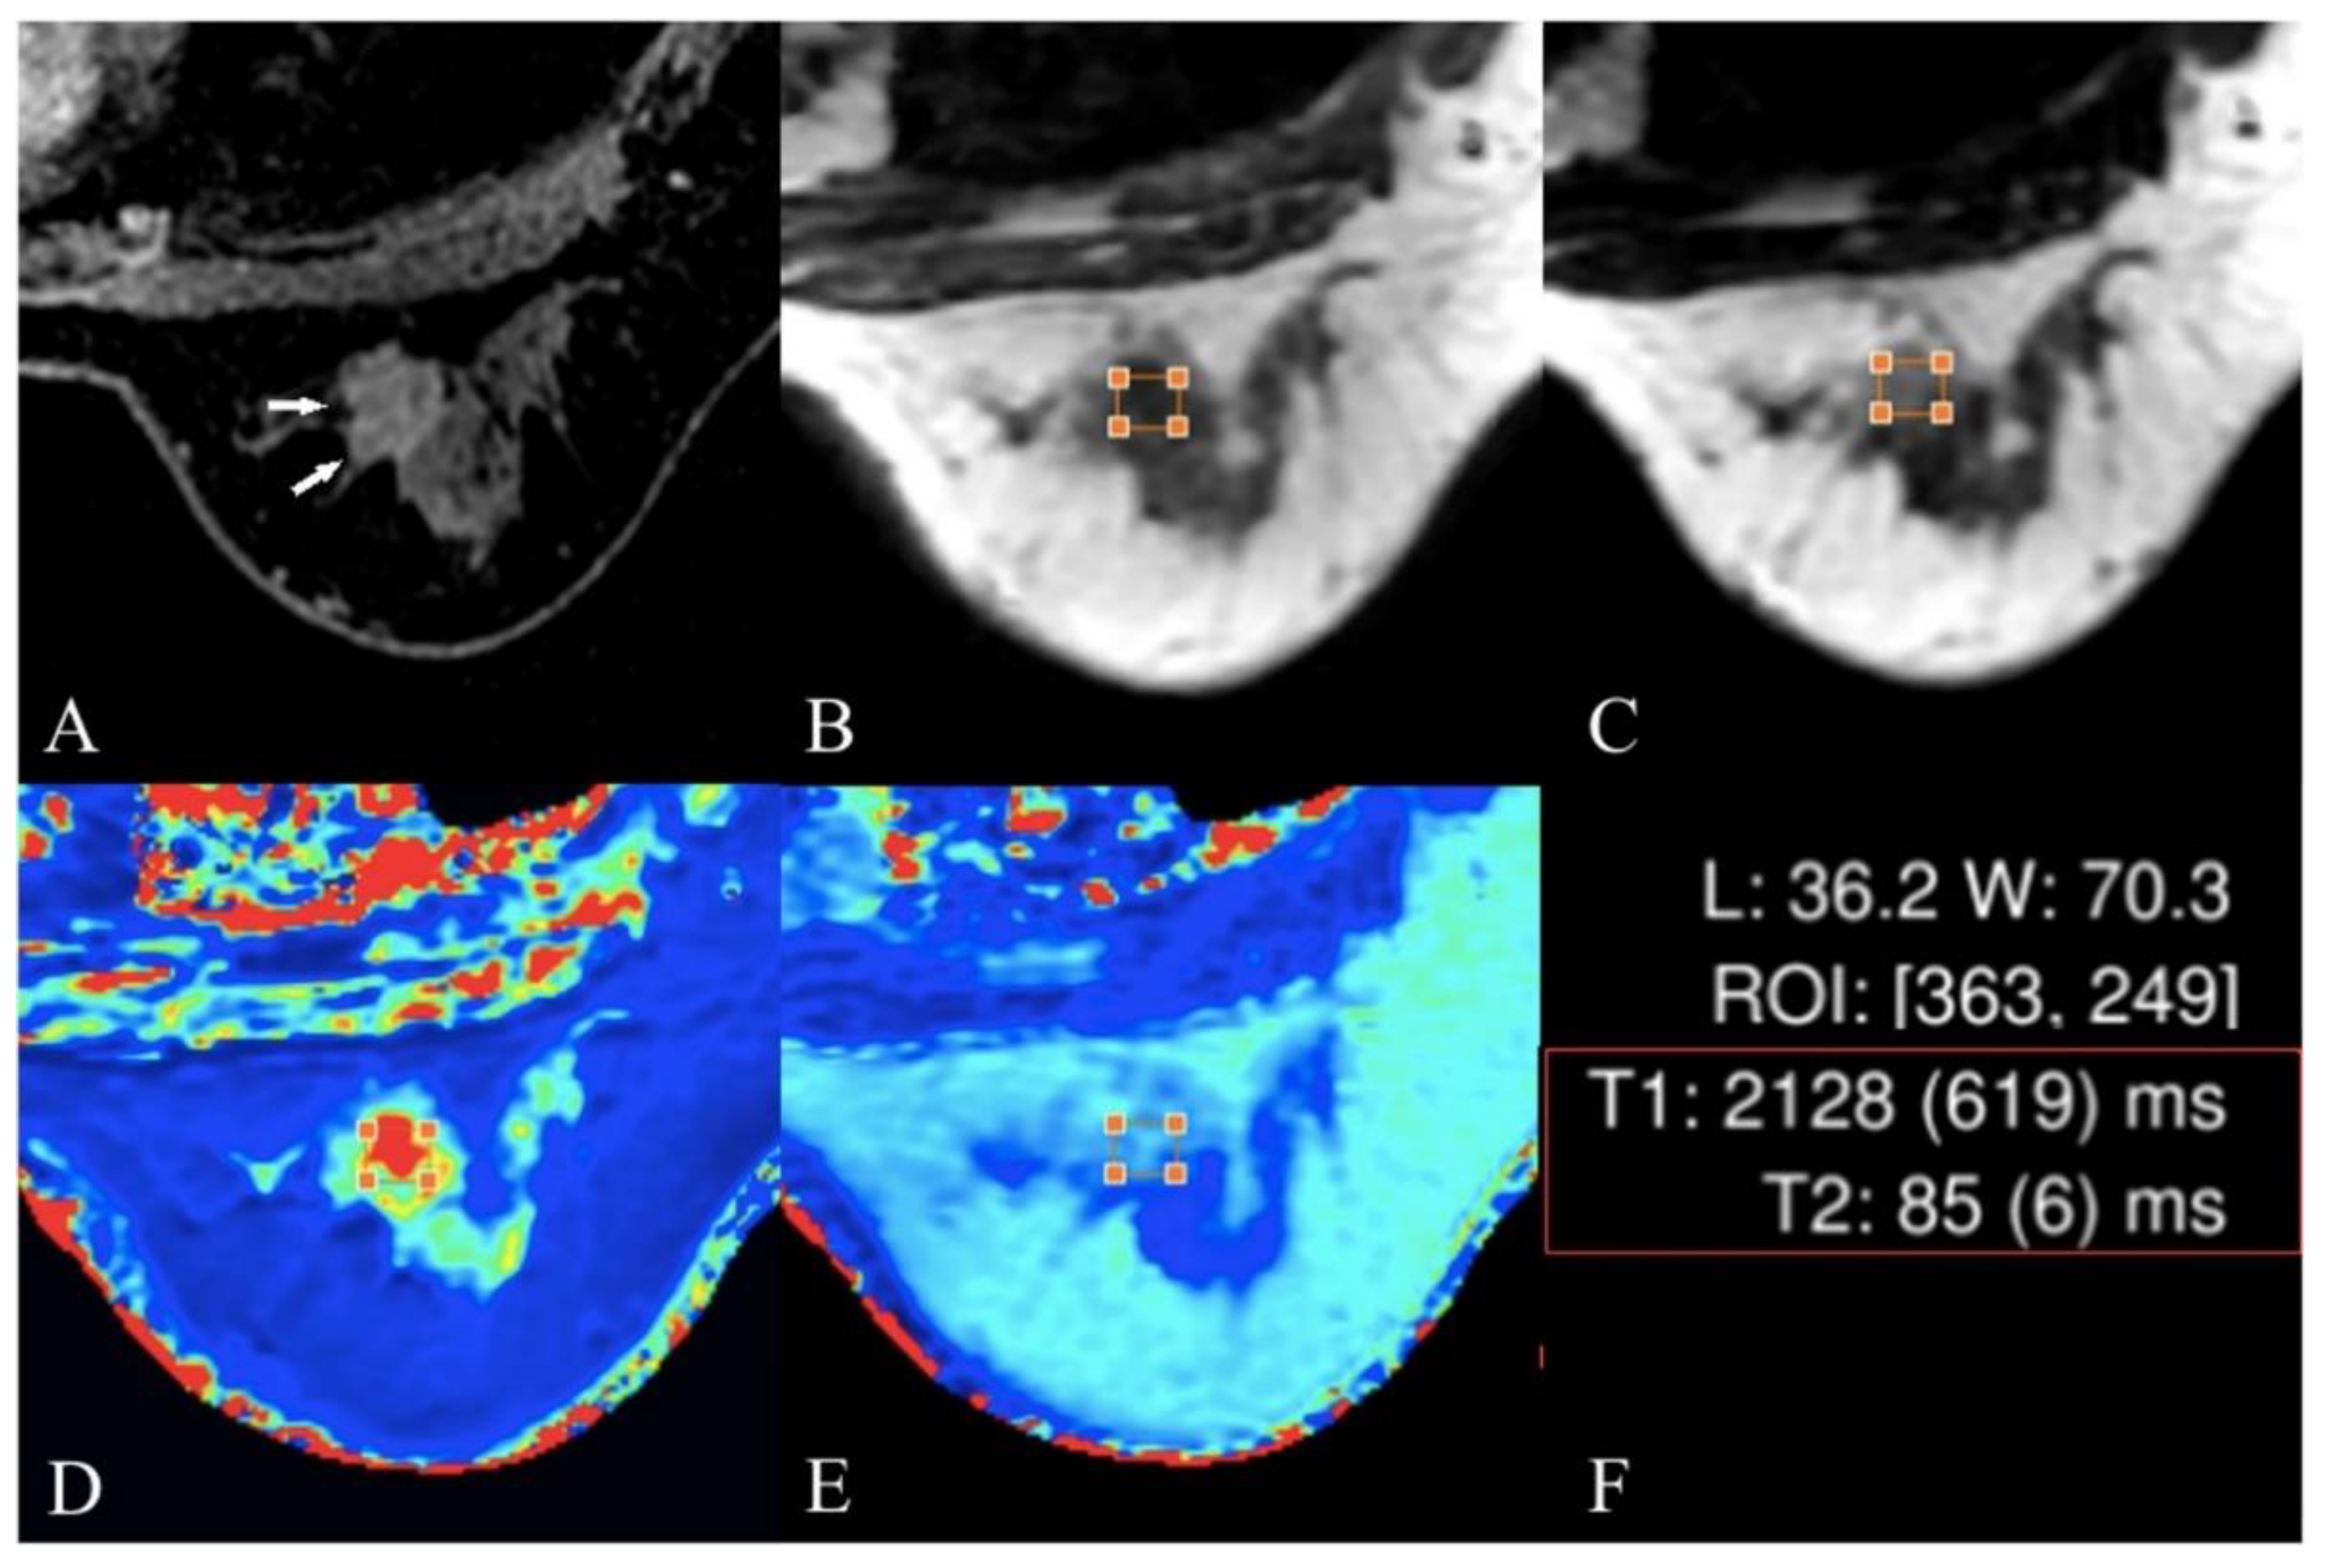

4.5. T2 and T2* Mapping

- Liu, L.; Yin, B.; Geng, D.Y.; Lu, Y.P.; Peng, W.J. Changes of T2 relaxation time from neoadjuvant chemotherapy in breast cancer lesions. Iran. J. Radiol. 2016, 13, e24014. [Google Scholar] [CrossRef]

- Seo, M.; Ryu, J.K.; Jahng, G.-H.; Sohn, Y.-M.; Rhee, S.J.; Oh, J.-H.; Won, K.-Y. Estimation of T2* relaxation time of breast cancer: Correlation with clinical, imaging and pathological features. Korean J. Radiol. 2017, 18, 238–248. [Google Scholar] [CrossRef] [PubMed]

- Liu, L.; Yin, B.; Shek, K.; Geng, D.; Lu, Y.; Wen, J.; Kuai, X.; Peng, W. Role of quantitative analysis of T2 relaxation time in differentiating benign from malignant breast lesions. J. Int. Med. Res. 2018, 46, 1928–1935. [Google Scholar] [CrossRef] [PubMed]

- Meng, T.; He, N.; He, H.; Liu, K.; Ke, L.; Liu, H.; Zhong, L.; Huang, C.; Yang, A.; Zhou, C. The diagnostic performance of quantitative mapping in breast cancer patients: A preliminary study using synthetic MRI. Cancer Imaging 2020, 20, 88. [Google Scholar] [CrossRef] [PubMed]